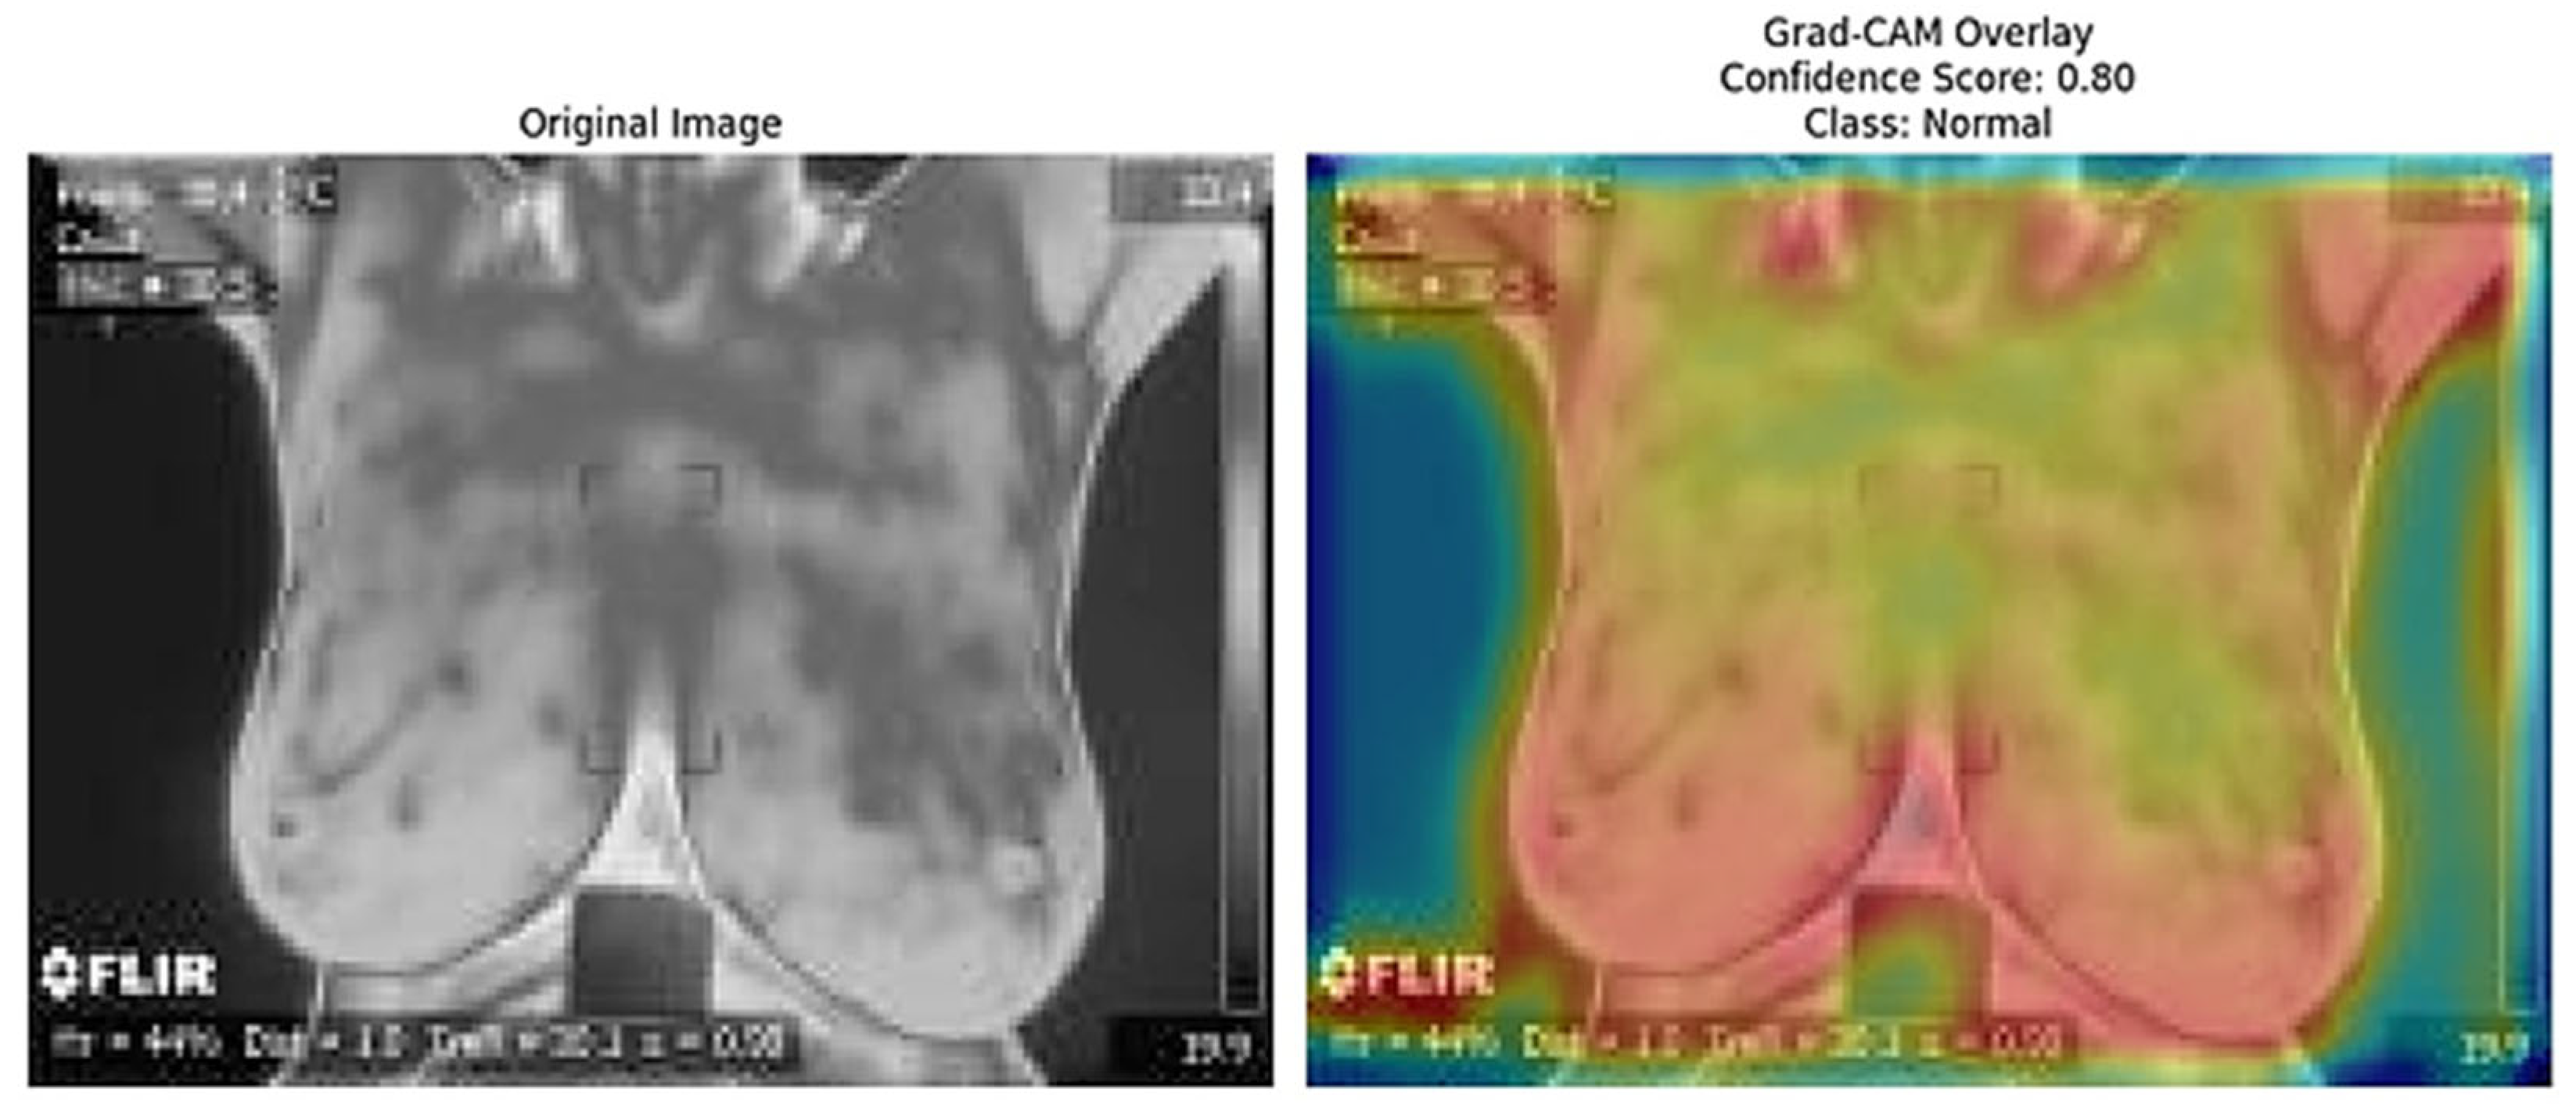

The Grad-CAM [41] overlays provide an essential layer of explainability to the ResNet152 + SVM model by highlighting regions of interest (ROI) that significantly influence the model’s predictions. These heatmaps, specific to each predicted class (e.g., normal, sick, malignant, benign), offer class-specific activation maps, shedding light on how the model differentiates among categories. By incorporating confidence scores (e.g., 0.80, 0.85) alongside these visualizations, clinicians can better understand and trust the model’s decision-making process. This approach directly addresses the “black-box” nature of deep learning models by visually explaining their predictions. Moreover, Grad-CAM overlays emphasize biologically relevant regions, such as abnormal heat patterns [56], as depicted in Figure 15, Figure 16, Figure 17, Figure 18 and Figure 19, enhancing the model’s interpretability and robustness in feature extraction. These insights validate the model’s focus areas against clinical knowledge and bridge the gap between AI-driven predictions and practical clinical applications, paving the way for greater trust and usability in real-world diagnostic settings.